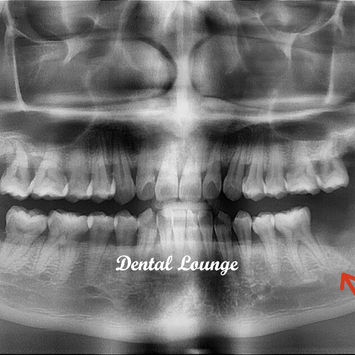

#38 is impacted with a severe food trap between #38 and #37.

CBCT taken reveals:

#37 has periodontal-endodontic involvement.

#38 is impacted.

#28 is non-functional.

Extraction of #38 was complicated with retained mesial and distal roots, unable to be fully extracted.

Additional CBCT was taken, and the inferior dental nerve (IDN) was traced.

Post-operative CBCT showed no remnants. IDN was spared.